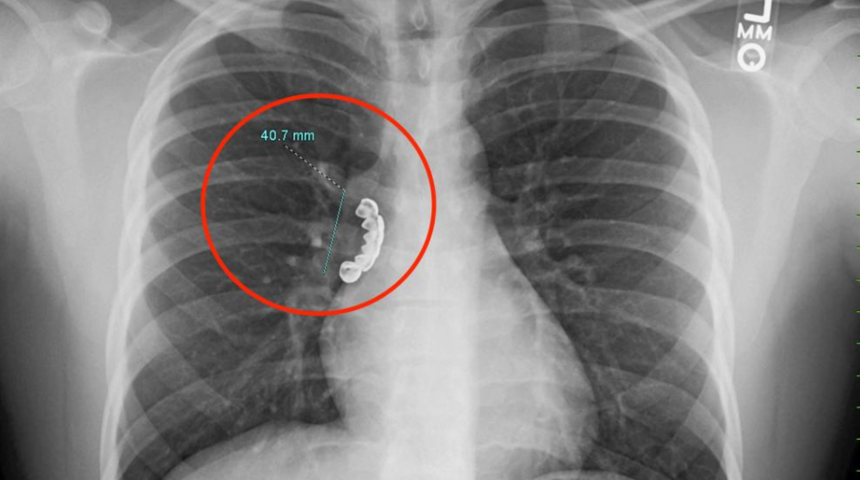

Amerika Birleşik Devletleri’nin Wisconsin eyaletinde yaşayan ismi açıklanmayan 22 yaşındaki bir adam epilepsi nöbeti geçirdi. Geçirdiği nöbetin sonrasında sürekli olarak devam eden öksürük krizi ve hırıltı sesi duyan genç adam hastaneye başvurdu. Hastanede çekilen röntgende genç adamın ciğerine sıkışan yaklaşık 4 santimlik bir takma diş fark edildi.

Cureus tıp dergisinde yayınlanan makalede vakada takma dişin hastanın akciğerin hava yoluna sıkıştığı belirtildi. Doktorlar takma dişi esnek bir tüp yardımıyla bronoskopi yaparak çıkarttı. Operasyon sırasında hastanın akciğer hava yolundaki kasların sıkışması anlamına gelen bronkospazm yaşadığı belirtildi. Hasta streoit tedavisinin ardından taburcu edildi.